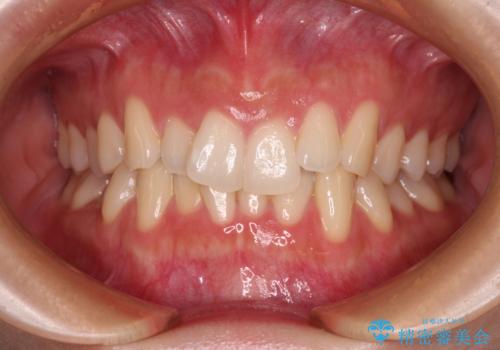

- 前歯の開咬と、上顎前歯の八重歯やデコボコを気にして来院された患者様です。

上顎歯列が狭窄していたため、急速拡大装置により上顎骨を側方に拡大し、その後ワイヤー装置にて矯正治療を行うこととしました。

上顎骨を拡大することで、八重歯やデコボコを歯列に収めることができ、下顎の歯が外に位置していた奥歯の咬み合わせも改善することができました。

スペースも短期間に獲得できるため、1年程度で治療を終えることができました。